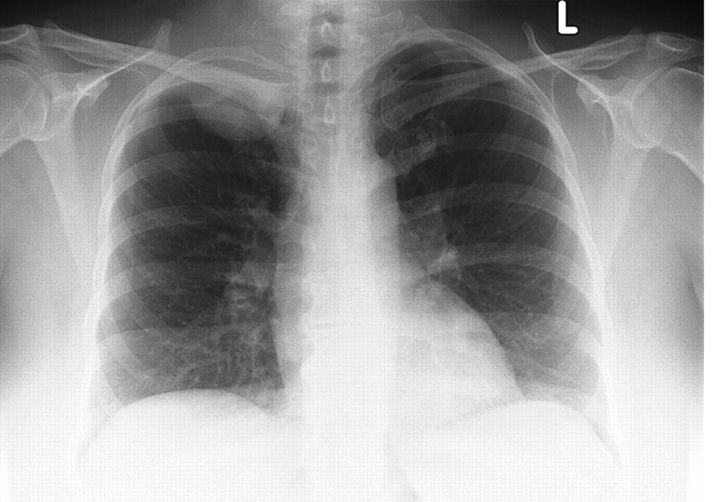

338) A 65 year old man presents to the Emergency Room with complaints of swelling of his face and worsening cough for the past two days. Swelling increases on lying down. He has no significant past medical problems. He smoked about 1 pack per day for the past 45 years and consumes alcohol socially. On examination, his vitals are satble with a blood pressure of 130/80 mm Hg. His face is grossly swollen and the veins over the neck, anterior chest and the face are engorged. There is no stridor. There is no laryngeal edema. Chest is clear to auscultation bilaterally. Cardiovascular examination shows normal s1 and s2 and there is no s3 gallop . A chest X-ray is shown below:

Which of the following is the most appropriate next step in management?

A) Radiation Therapy

B) Chemotherapy

C) CT guided Per-cutaneous Needle Biopsy

D) Video-Assisted Thoracoscopic Surgery (VATS)

E) Endotracheal Intubation

Filed under: Uncategorized, USMLE Test Prep | Tagged: Archer cardiology, Archer oncology, Archer pulmonology, Archer radiology, USMLE STEP 3 CARDIOLOGY, USMLE STEP 3 ONCOLOGY, USMLE STEP 3 PULMONOLOGY, USMLE STEP 3 RADIOLOGY | 12 Comments »